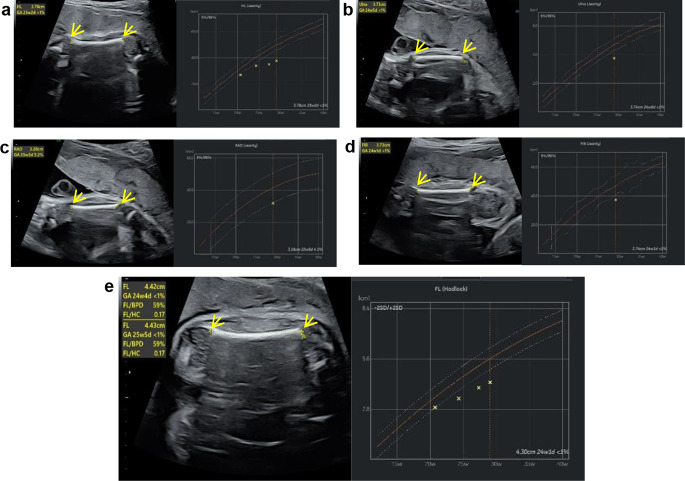

Brachydactyly A1 (BDA1) is a rare disorder characterized by the disproportionate shortening of fingers and/or toes with or without symphalangism. Mutations in Indian hedgehog signaling molecule (IHH), which impair the effect of functional IHH protein derived from its precursor IHH, are commonly identified in patients with BDA1 or acrocapitofemoral dysplasia (ACFD). The ultrasound phenotype of fetuses with IHH mutations has rarely been described. To better understand the consequences of IHH mutation, we analyzed the characteristics of a Chinese fetus with BDA1 caused by a novel heterozygous IHH mutation. Clinical data and genomic DNA were collected from the proband and family members. Whole-exome sequencing (WES) was performed to identify potential causative mutations. Sequence analysis was performed to investigate the conservation of the affected leucine residue in IHH. Protein 3D modeling was performed to predict the effects of the mutation on protein structure. In vitro overexpression transfection experiments in human embryonic kidney 293T (HEK293T) cell lines were performed to evaluate the pathogenicity of the identified mutation. The fetal proband carried a novel heterozygous mutation in IHH (NM_002181.4: c.331_333delCTG, NP_002172.2: p.Leu111del) inherited from the father; this mutation manifested as shortening of the limbs, with more severe shortening observed in the proximal extremities than in the distal extremities, as evidenced by ultrasound. The Leu111 residue is highly conserved among vertebrates, and deletion of this residue destabilizes the protein structure. Western blotting analysis of HEK293T cells in overexpression transfection experiments revealed that the Leu111del mutation led to an increase in the level of the IHH precursor and a reduction in the level of functional IHH protein compared with those in HEK293T cells expressing wild-type IHH, indicating that this mutation might cause IHH protein dysmaturity. The novel heterozygous mutation c.331_333delCTG (p.Leu111del) in the IHH gene is the likely cause of BDA1 in this Chinese fetus. This mutation causes IHH protein maturation failure. These findings contribute to our understanding of the molecular pathogenesis of BDA1 and the clinical identification of fetal BDA1.